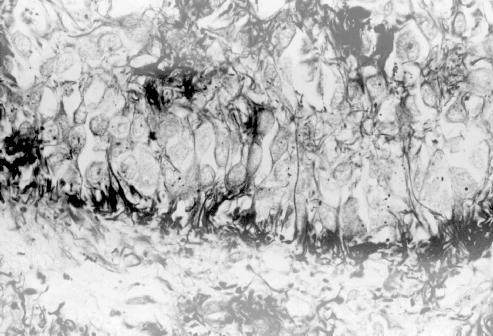

Rio-Hortega stain

Bulbous endings of human pinealocytes in contact with

the intervening capillary stroma (lower half)(Rio-Hortega stain)